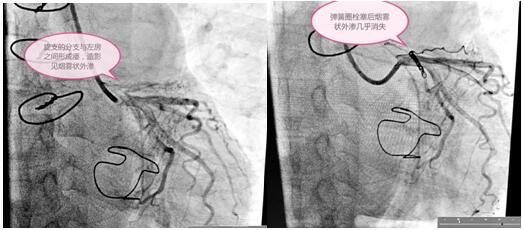

定于3月3日進(jìn)行冠狀動(dòng)脈瘺彈簧圈栓塞手術(shù),術(shù)前手術(shù)團(tuán)隊(duì)為患者細(xì)心指導(dǎo),消除患者緊張情緒,穿著手術(shù)衣,帶著一次性手術(shù)帽和普通外科口罩,做好防護(hù)。吳棟梁院長(zhǎng)和高勝利主任手術(shù)團(tuán)隊(duì)為患者精心進(jìn)行了手術(shù),要將大小合適的彈簧圈放在血管遠(yuǎn)端狹窄處封住瘺口,患者冠脈及分支血管比較迂曲,會(huì)導(dǎo)致手術(shù)過(guò)程比較復(fù)雜,耗時(shí)長(zhǎng),這些在手術(shù)方案里均考慮到。初始常規(guī)使用的導(dǎo)絲通過(guò)困難,后來(lái)根據(jù)患者血管走形我們又選擇了微導(dǎo)管和特殊的導(dǎo)絲,導(dǎo)管室很安靜,能聽(tīng)到的只有時(shí)鐘的滴答聲和我的心跳聲,調(diào)整了手術(shù)器械后彈簧圈很快送到位并釋放,手術(shù)終于圓滿(mǎn)結(jié)束,比我們預(yù)計(jì)的手術(shù)時(shí)間提前了半小時(shí)。

術(shù)前與術(shù)后